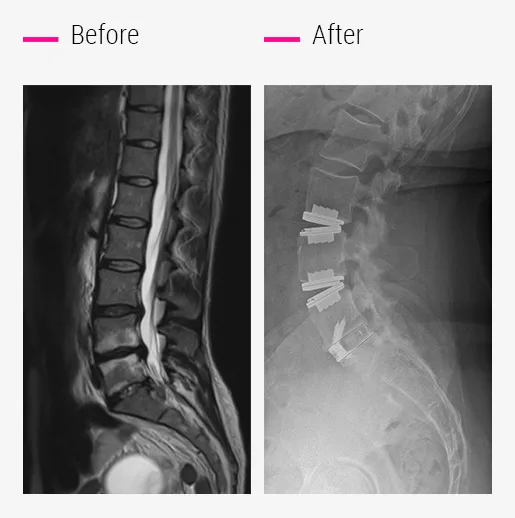

What to do about recurrent herniation?

These symptoms sometimes occur in people who have undergone discectomy surgery for one or more herniated discs.

It is important to understand that the purpose of a discectomy is to relieve the compression of the nerve by disc fragment ejected from its housing, but it does not treat the disc disease responsible for the herniation, which will continue to progress.

- Prodisc-L® total disc replacement treats the diseased disc and the hernia in a single operation.